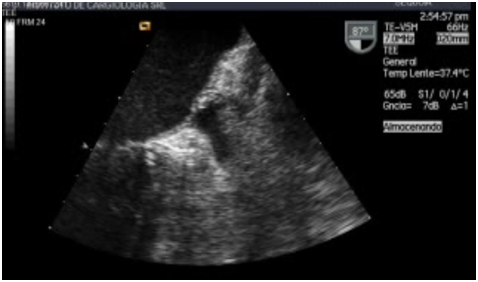

The patient was in the left lateral decubitus under deep sedation and with oropharyngeal anesthesia with xylocaine, TEE was performed with a multi planar probe. At the middle esophageal level, with an angle of 87degrees, it was possible to verify that the morphology of the LAA corresponded to the chicken wing type, with a size of 4.3 cm2 of area. It was noted that at the connection site between the LAA and the Left Atrium (LA) a ¨septum¨ that closure LAA. This structure showed no movement and when it was explored with color Doppler, it was found that it had a narrow perforation through which a high-speed bidirectional flow proceeded (Figure 2-5). In the interior of the appendage, there was no evidence of spontaneous contrast echo or thrombi.

Figure 2 TEE at the mid-esophageal level, with an angle of 87 degrees. We can see the left atrial appendage (LAA) (thick arrow), and the septum that is in the connection site of the appendage with the left atrium (thin arrow).